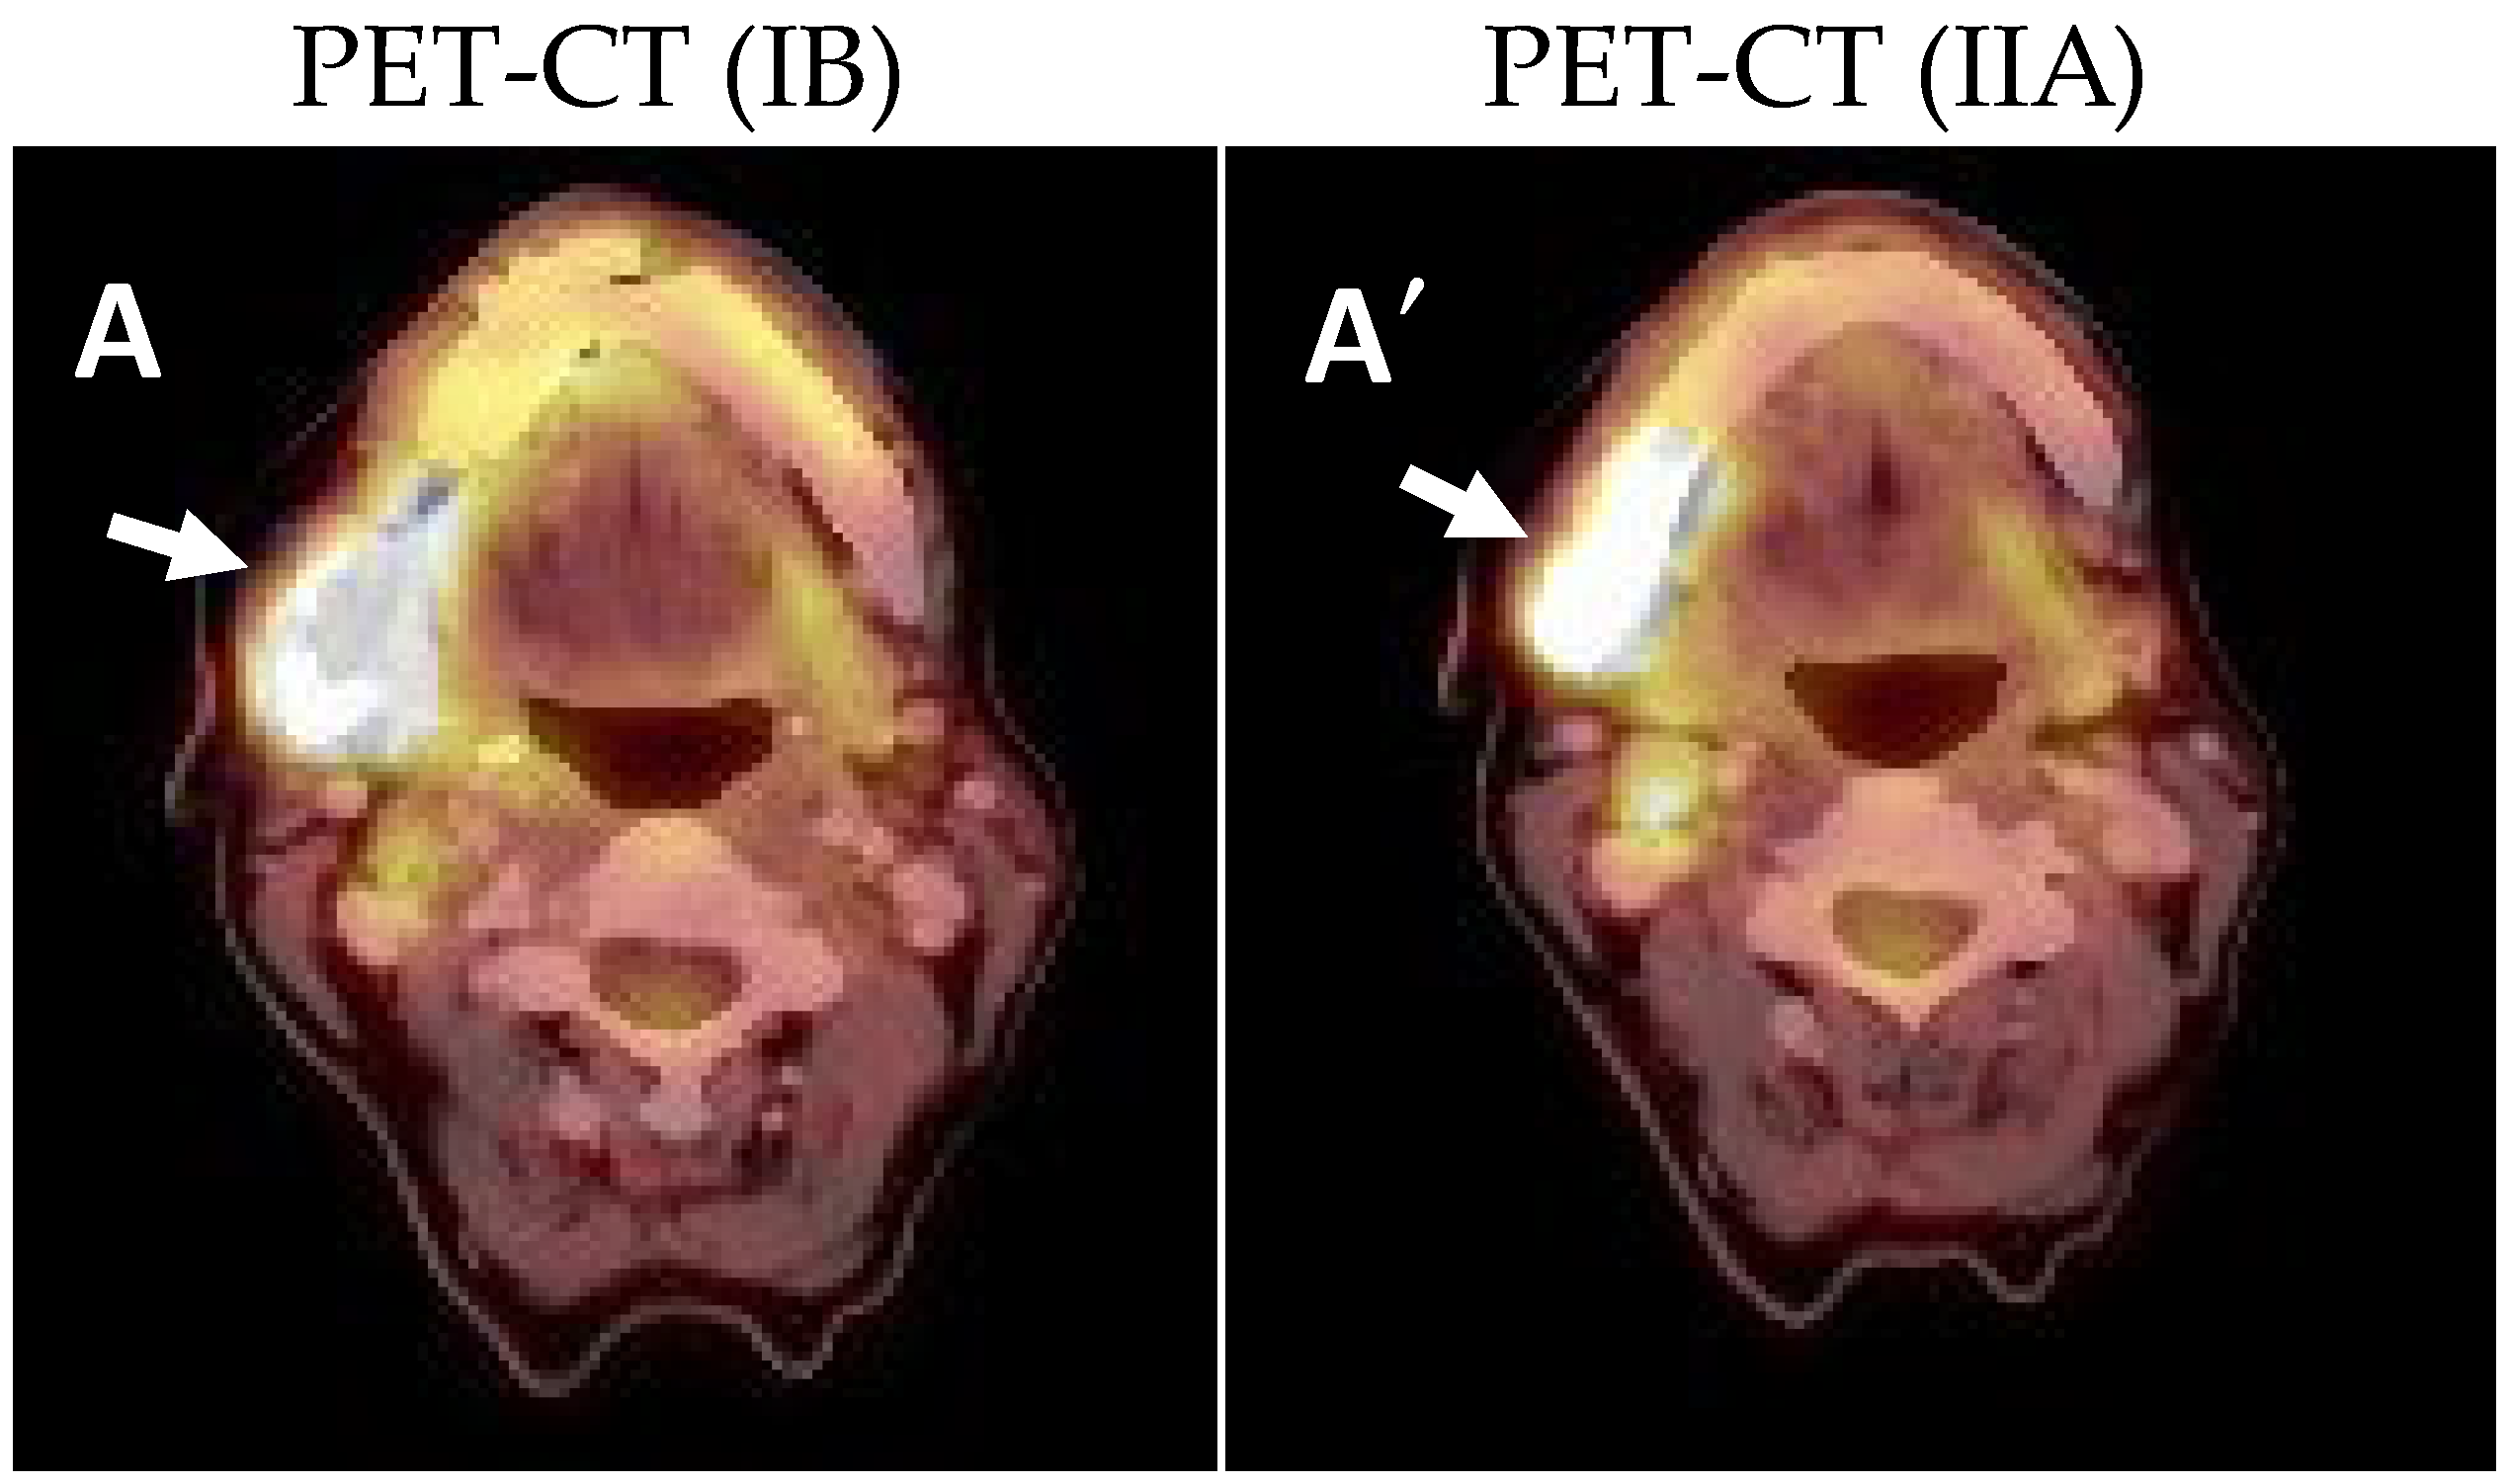

2.1. Clinical and Histological Manifestations of the Tumors